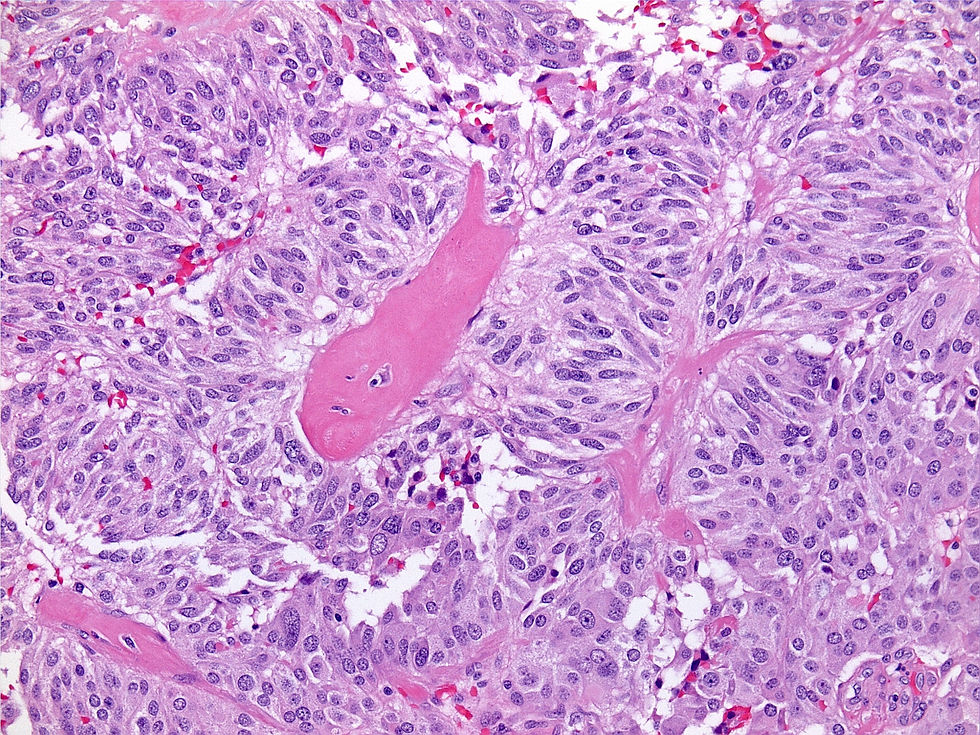

Here is a case from Dr. Denham's files. This is a 53-year-old male with a large thyroid mass.